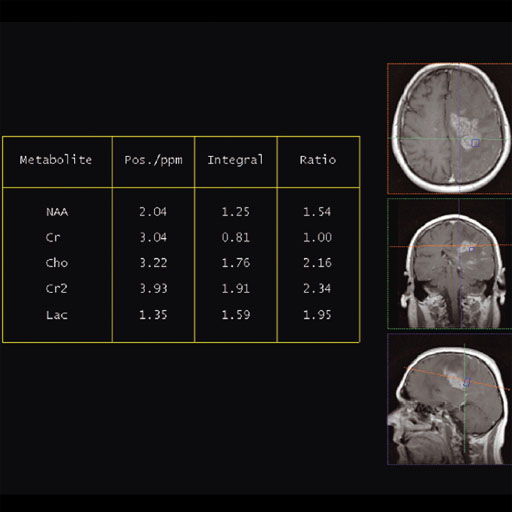

The prostate spectroscopy package is an comprehensive

software package which bundles:

- Single Voxel Spectroscopy

- 2D Chemical shift Imaging

- 3D Chemical Shift Imaging

- Spectroscopy Evaluation syngo

- syngo Tissue 4D Evaluation

Sequences and protocols for proton spectroscopy, 2D and 3D

proton chemical shift imaging (2D CSI and 3D CSI) to examine

metabolic changes in the prostate are included. Furthermore

included is the comprehensive Spectroscopy evaluation software

which enables fast evaluation of spectroscopy data on the syngo

Acquisition Workplace.

Tissue 4D is an application for visualizing and post-processing

dynamic contrast-enhanced 3D datasets.

Tissue 4D provides two evaluation options:

- Standard curve evaluation

- Curve evaluation according to a pharmacokinetic model.

The spectroscopy evaluation software is fully integrated in

syngo MR.

Evaluation protocols adapted to the scan protocols carry out a

complete and automatic evaluation of the measured data.

Optimized protocols for 3D CSI in the prostate are included.

The following functions are included:

- Subsequent water suppression with optional phase correction

- Apodization

- Zero filling

- Fourier transformation

- Base line correction

- Automatic or manual phase correction

- Curve fitting and peak labeling

- Summaries in tabular form of the essential results specifying

the metabolites, their position, integrals and signal ratios in

relation to a selectable reference.

- 3D CSI (Chemical Shift Imaging):

Integrated multivoxel spectroscopy software package with

sequences and protocols for 3D Chemical Shift Imaging (CSI). Features Matrix Spectroscopy – phase-coherent signal combination from

several coil elements for maximum SNR with configurable

prescan-based normalization for optimal homogeneity 3D Chemical Shift Imaging Hybrid CSI with combined Volume selection and Field of View

(FoV) encoding Short TEs available (30 ms for SE, 20 ms for STEAM) Automized shimming of the higher order shimming channels for

optimal homogeneity of the larger CSI volumes Weighted acquisition, leading to a reduced examination time

compared to full k-space coverage while keeping SNR and

spatial resolution Outer Volume Suppression Spectral Suppression Protocols for prostate spectroscopy Clinical Applications Prostate Spectroscopy for diagnosis, localization of

prostate cancer Improved spatial localization of metabolic changes in biopsy

or radiotherapy planning

| Cho/Cr ratio map generated from

3D CSI measurement |

Spectral nap generated from 3D

CSI measurement |

Increased Cho-signal in a

medulloblastoma case |